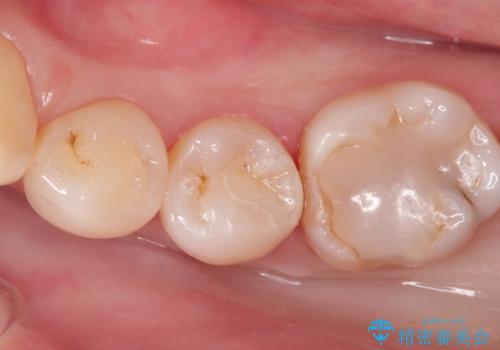

- 定期検診において虫歯を見つけた患者様です。

セラミックインレーにて修復治療をしています。

当院のセラミックインレーはすべてプレスという製法で製作しております。削り出しのものより精度が高く製作可能です。